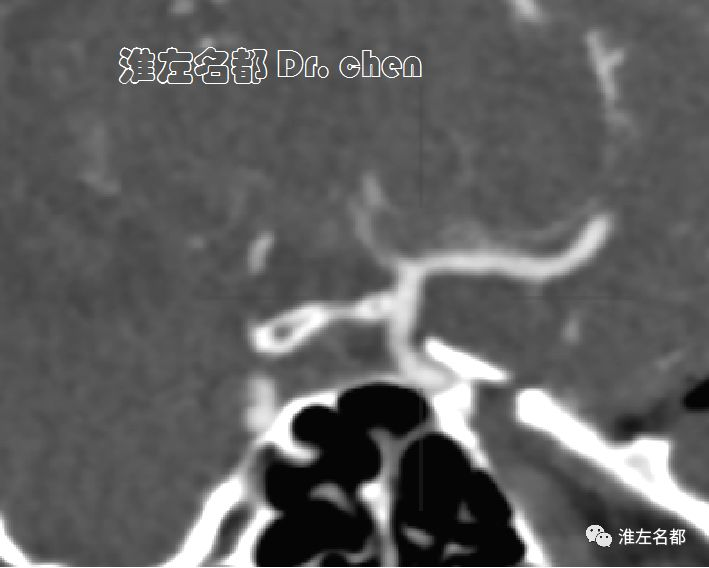

△头颅CTA:左侧颈内动脉末端和大脑中动脉未见显影;左侧颈内动脉显影较右侧细小,造影剂浓度淡(提示血流缓慢)。

△脑CTP静脉早期多平面重建:左侧大脑中动脉主干显影细小(红箭)